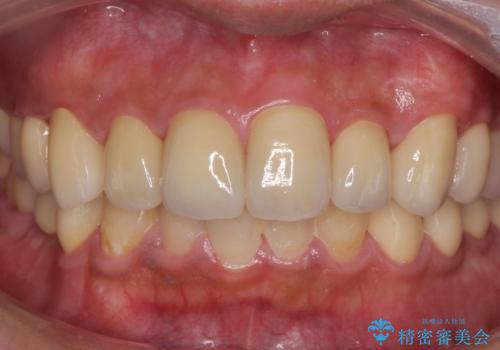

適合の良い被せ物、インプラントが入りました。

全ての治療が終わった後はNG(ナイトガード)を使用し、定期的にメンテナンスに

くることをお勧めしたいます。